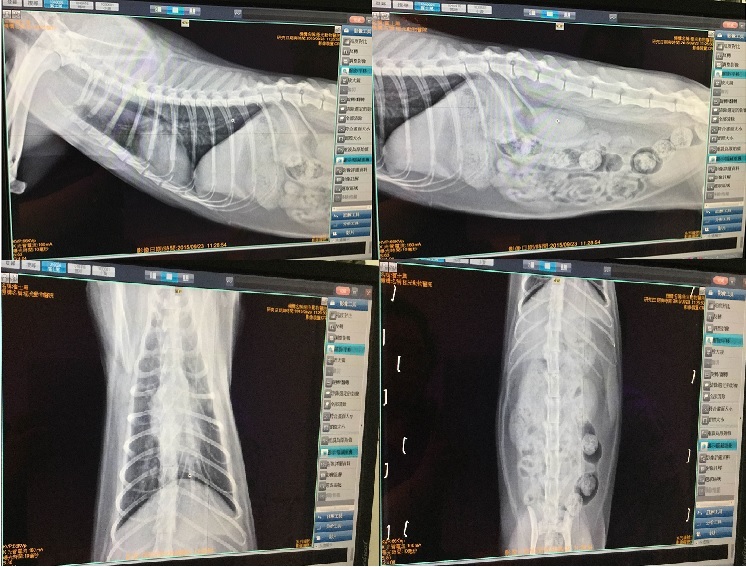

口腔的部分,傷口直接採樣檢查,呈現早期鱗狀細胞瘤的現象,但也有可能是因自體免疫系統問題而造成嚴重口炎,故另外在口腔傷口採樣送病理檢查以確診,X光可見肺部目前是未受影響的,先拿2週口服藥,2週後回診看報告,視報告結果決定治療的方向。動物近況說明: 膽子小的麵魯好不容易順利過了年初的難關,在安養之家安心的生活才半年,卻又有嚴重口炎現象,飲食出現問題,目前正盡力幫麵魯治療,幫麵魯恢復健康的醫療費用,希望大家幫忙。